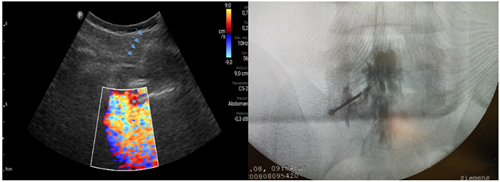

Los procedimientos fueron realizados en sala de operaciones, con vía venosa periférica y en posición decúbito ventral. Los mismos fueron realizados por el investigador principal (P. C.) con experiencia en la realización de procedimientos ecoguiados en la columna vertebral, utilizando la técnica paramediana en eje ecográfico corto. Se utilizó un ecógrafo portátil modelo Lumify marca Phillips, con transductor curvo de baja frecuencia. Fundas y gel ecográfico de la marca Pajunk® (Pajunk GmbH Medizintechnologie, Geisingen, Germany). En cada caso se identificó el espacio L4-L5 o L5-S1 mediante escaneo ecográfico de la columna lumbosacra en el plano transversal y longitudinal previo al inicio del procedimiento. Con la sonda ecográfica colocada en plano transversal o en eje corto, se realiza un habón anestésico 1 a 2 cm a un lado del transductor, correspondiente al lado del dolor radicular. La aguja de Tuohy ecogénica, 18 G (Tuohy Sono, 18G Pajunk® GmbH Medizintechnologie, Geisingen, Germany) de 9 o 12 cm según la contextura del paciente, se dirige en plano, en tiempo real, en sentido lateral a medial, entre la articulación facetaria por fuera y el ligamento interespinoso por dentro, hasta alcanzar el ligamento amarillo, en el espacio interlaminar elegido (Figura 1). El espacio epidural fue identificado mediante la pérdida de resistencia con suero fisiológico. Se registró la imagen doppler color durante la maniobra, como medida alternativa a la epidurografía con contraste (Figura 2). Posteriormente, 5 cc de contraste no iónico fue inyectado. Se consideró que fue alcanzado dicho espacio cuando el contraste se distribuye a lo largo del ligamento longitudinal posterior (Figura 2). 1 mg/kg de triamcinolona más 3 cc de lidocaína al 0,5 (hasta 10 cc de solución total) se inyectan en el espacio epidural.

Fig. 2. Inyección de 5 a 10 ml de suero fisiológico con registro de la imagen doppler color, que se distribuye en el canal raquídeo, en una inyección epidural L5S1 paramediana derecha (imagen a la izquierda). Las flechas azules indican el trayecto de la aguja de Touhy. A la derecha se observa la confirmación con epidurograma de una inyección epidural L5S1 izquierda.